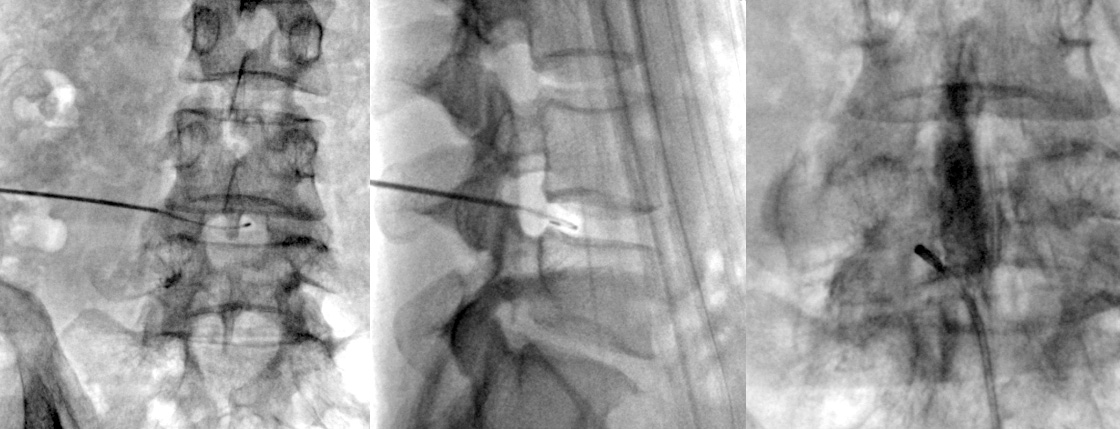

직경 2mm 이내의 가느다란 주사바늘을 문제가 생긴 디스크에 병변에 고주파에너지를 쏘아 척추신경을 압박하는

디스크내의 분자를 분해하고 녹인 후 수축 응고시키는 치료 방법입니다.

전신마취가 아닌 부분 마취 후 간단한 시술방법으로 조기 보행이 가능하고, 심하게 무너진 척추골의 높이를 교정할 수 있습니다.

회복기간도 짧아 많이 적용되는 치료 방법입니다.